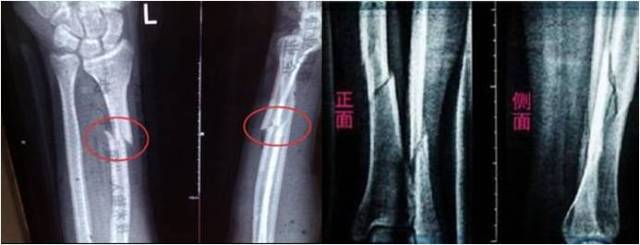

解剖复位是指复位后,完全恢复正常解剖形态,也就是断端对得“严丝合缝”。这是最理想的复位结果。但往往是理想很丰满,现实很骨感。有时候医生虽尽最了大努力,骨折仍未能“严丝合缝”,但愈合后对肢体功能无明显影响者,称功能复位。

过去的很多年里,为达到解剖复位,手术时采取大切口,广泛显露,骨块血运破坏大,出现了很多骨折愈合慢或不愈合的情况,不得不再次或多次手术,患者非常痛苦。随着观念的改变,微创理念深入人心,手术已经不再是大刀阔斧的时代了。切口一般较小,骨折断端一般不显露,这样可以尽量不加重骨折部位的损伤,有利于骨折愈合。患者功能恢复快,痛苦少。因此,正确的做法是在充分保护断端血供的前提下,争取解剖复位。但不能以破坏断端血供为代价来强求解剖复位,这样得不偿失,此时满足功能复位条件即可接受。

3.成角移位:下肢:轻微地(成人不超过10度,儿童不超过15度)向前或向后成角,与关节活动方向一致,日后可在骨痂改造期内自行矫正。向侧方成角移位,与关节活动方向垂直,日后不能矫正,必须完全纠正。否则关节内、外侧负重不平衡,易引起创伤性关节炎。上肢:肱骨干稍有畸形,对功能影响不大;前臂双骨折则要求对位、对线均好,否则影响前臂旋转功能。关节内骨折需解剖复位。

4.长骨干横形骨折,骨折端对位至少达l/3左右,干骺端骨折至少应对位3/4左右。